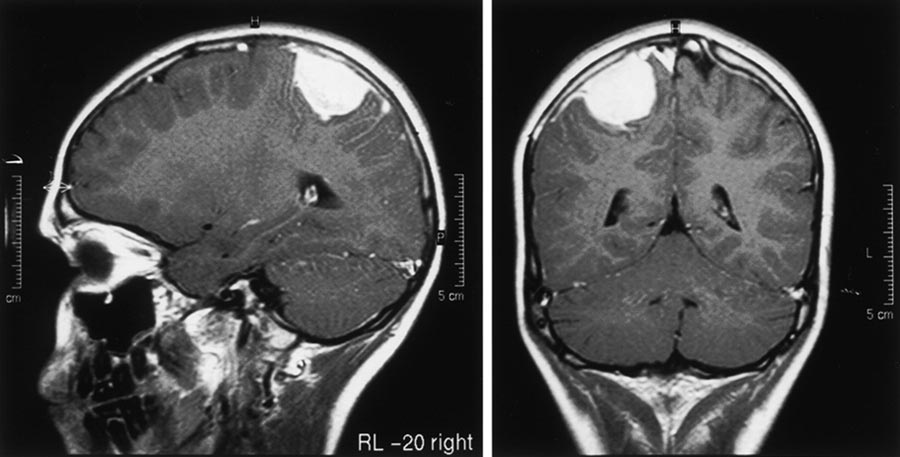

Meningiomas are brain tumors, usually benign, that starts in the cells that cover the surface of the brain. They grow in the region of the cerebral hemispheres or at the level of the cranial base (meningioma of the cavernous sinus), and are characterized by rather slow growth and in most cases without infiltration of the brain tissue that surrounds them.

Among the first manifestations of meningioma, is epilepsy and alterations of behavior. Depending on the precise location of the meningioma, there may be difficulty speaking or moving an arm or leg. The headache which is the most common symptom for many other brain diseases, in this case, is rather rare. In some cases, discoloration of the scalp may also occur at the site of the meningioma, which takes the form of the meningioma itself. They are rounded and have a diameter of a few centimeters.

Often the diagnosis of meningioma occurs in a completely random manner when tests are prescribed such as MRI or CT scan to check other ongoing problems (for example for a history of headache or a head injury). This happens because in 70% of the cases the meningiomas are asymptomatic.

Once the diagnosis of meningioma has been ascertained, the neurosurgeon can evaluate different treatment options that mainly depend on the nature of the pathology.

The first therapeutic indication is usually represented by the surgical intervention that allows the total or partial removal of the tumor. In the case of meningiomas of the skull base, and in particular of the cavernous sinus, the treatment of stereotactic radiosurgery with Gamma Knife is beneficial, which allows excellent control of tumor growth with very low risks. Radiation therapy, on the other hand, is indicated in the presence of an aggressive meningioma or as a complement to surgery.

Gamma Knife radiosurgery is a technique for intracranial stereotactic radiosurgery. It can be useful for intervening on primitive brain tumors, such as meningiomas. Treatment with Gamma Knife allows targeting the meningioma with a beam of radiation.

The patient will be slightly sedated, then the stereotaxic helmet will be applied to him with local anesthesia. He will be subjected to MRI tests of the brain with gadolinium. These images allow the specialist to plan the treatment. Once the plan is completed, the patient will be lying down with the stereotaxic helmet attached to the Gamma Knife couch. The procedure can last from one to six hours, depending on the patient’s needs and the target to be irradiated.

Patients with meningiomas that do not exceed 3.5 cm in diameter may be treated.